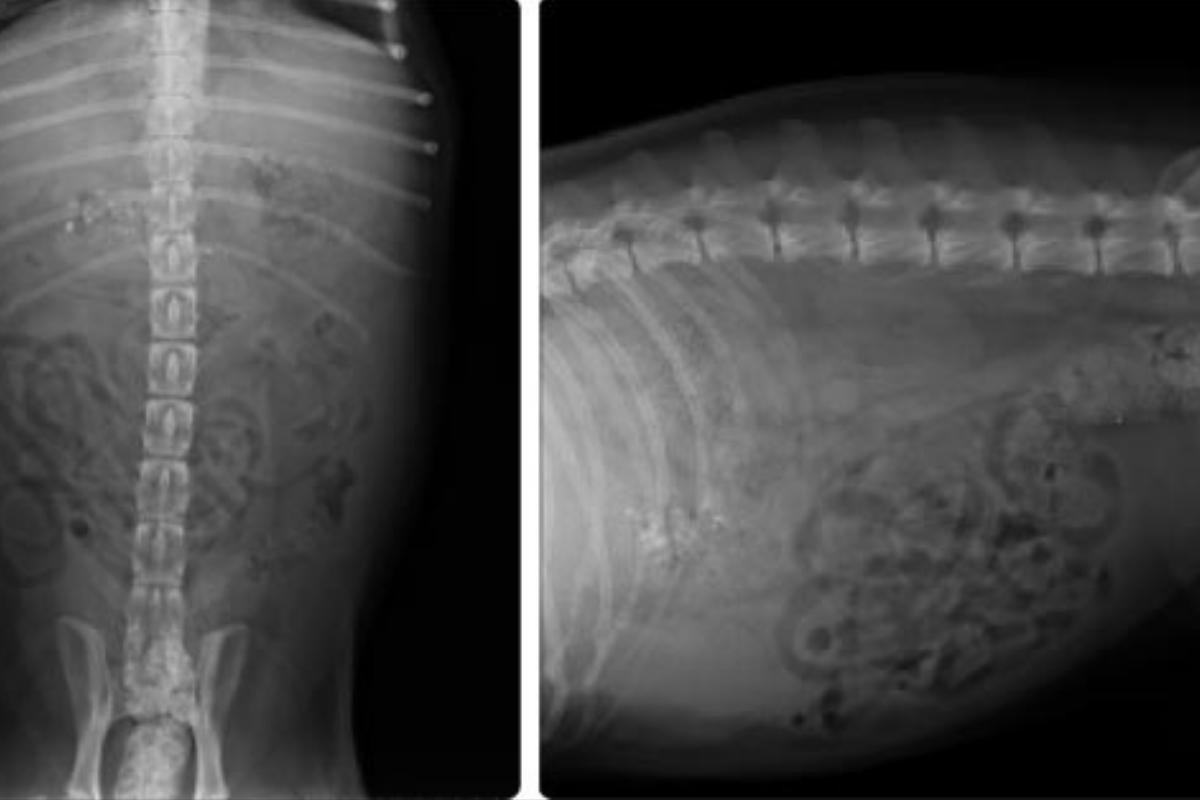

El diagnóstico de la peritonitis no es solo realizado por las manifestaciones clínicas, como la observación de los síntomas y la historia del perro. El veterinario también realizará otras pruebas diagnósticas que se complementan con el examen físico, como radiografías, estudios de la sangre y de las urine, para determinar la causa de la enfermedad.

El diagnóstico de la peritonitis en perros no es solo realizado por las manifestaciones clínicas, como la observación de los síntomas y la historia del perro. El veterinario también realizará otras pruebas diagnósticas que se complementan con el examen físico, como radiografías, estudios de la sangre y de las urine, para determinar la causa de la enfermedad.

Las radiografías son una de las pruebas diagnósticas más comunes para detectar la peritonitis. Las radiografías pueden detectar el dolor abdominal, la inflamación y el edema en las partes afectadas por la peritonitis.